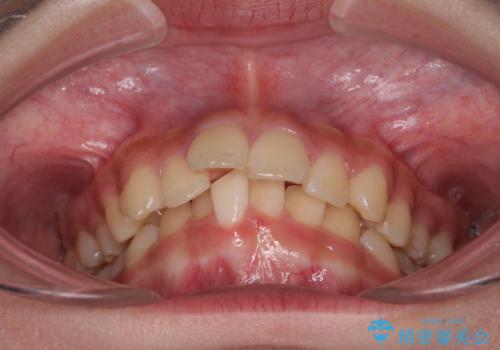

- 前歯の叢生と深い咬み合わせを気にして来院された患者様です。

奥歯の咬み合わせを見ると、上顎が下顎に対して相対的に前方にありました。

深い咬み合わせを改善するためには、上顎臼歯を後方に移動させつつ、下顎の小臼歯を直立させる必要があります。